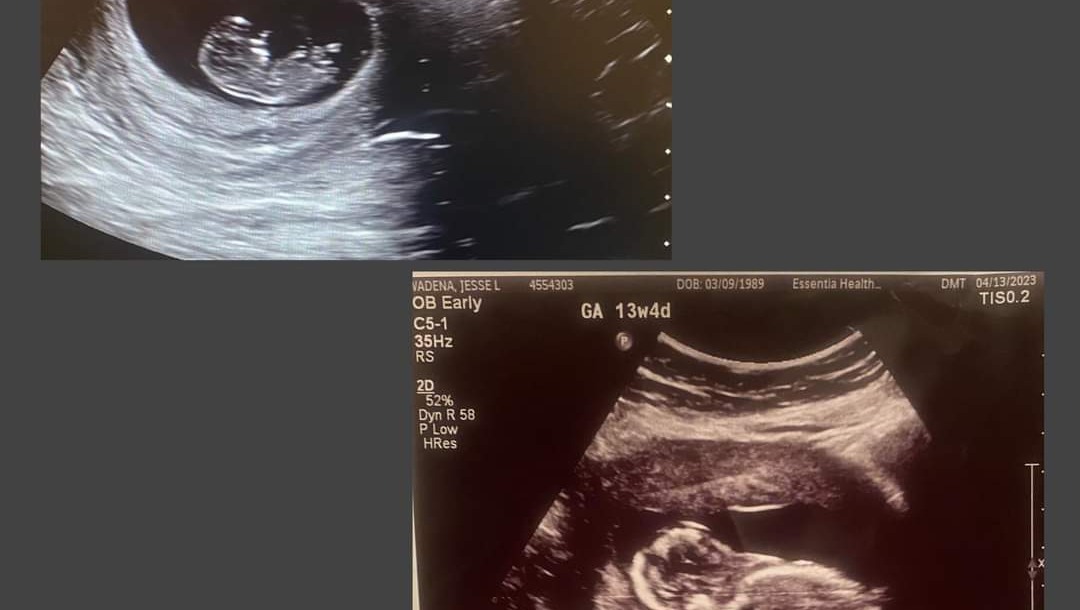

"So baby has something causing blockage from his bladder into his urethra and its causing fluid backup around/in his kidneys. It’s nothing that could have been prevented by me, just something that sometimes happens. Without the flow of fluids out of his kidneys it’s causing swelling and could damage kidneys.

So there’s the fluid build up…but also low amniotic fluid around baby. Baby not getting enough amniotic fluid can cause his lungs not to develop. So without intervention care he may develop the need for dialysis or other kidney issues after birth, and low amniotic fluid can cause lungs not to develop strongly there were 3 options she gave me for next steps - termination of pregnancy or no treatment and go with whatever happens happens, or get a shunt and basically get his urine/fluids out for him. A shunt is the most recommended and they’ll closely monitor baby’s development and response to it. They can also do a genetic test to see whether there are any other factors involved but highly likely it’s just a blockage in his urethra (pee passage) the shunt would help with that. And then I’d possibly develop more amniotic fluid and his lungs would have a better chance of developing so he’d have more room to grow. Also if fluid stays low it could possibly cause club foot or other issues with limbs because baby has less room to move around and get things functioning but that would all be treated after birth if it were to happen. Baby’s blockage would need to be treated after birth too but the surgery I need would help him get fluids out of his kidneys while he’s in my belly. I would have to have the shunt put in at Mayo in Rochester. And be monitored possibly weekly in Fargo after that.